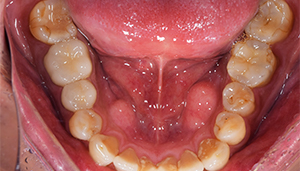

治療後:下の歯

担当医師所見:

下顎右側第1大臼歯は抜歯後、仮歯に置き換え治癒を待った後ジルコニアステイニングBrにて補綴。 全顎的に色調・形態共に調和がとれている。